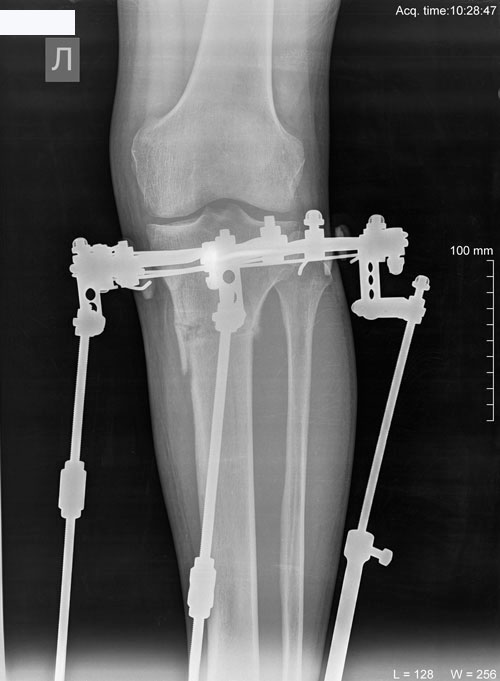

Рентген в 56 дней.

Сращение идёт отлично!

П1.jpg

П2.jpg